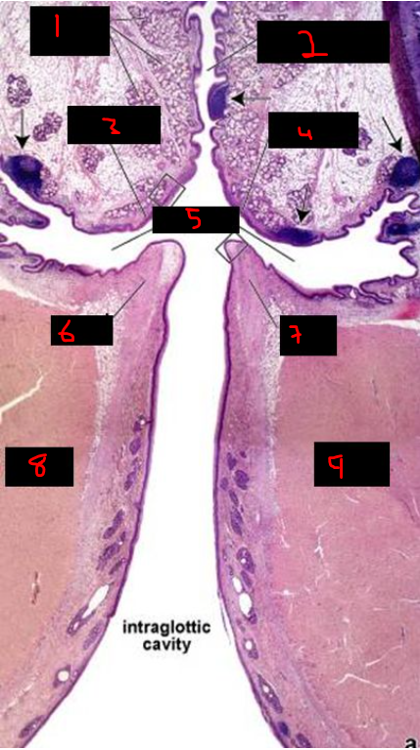

39

card image

What is 3?

pharyngeal tubercle

40

What is 4?

styloid process

41